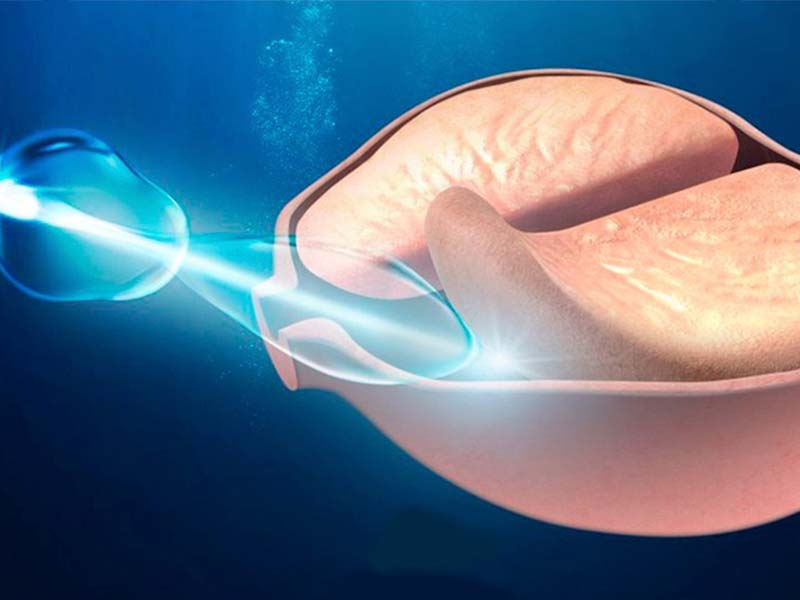

ENUCLEAÇÃO DE PRÓSTATA COM LASER HOLMIUM (HOLEP)

A HoLEP (Holmium Laser Enucleation of the Prostate) é uma técnica moderna e minimamente invasiva para o tratamento do **crescimento benigno da próstata (HPB – Hiperplasia Prostática Benigna).

💡 Por que optar pelo HoLEP?

✅ Procedimento com alta precisão e segurança

✅ Menos sangramento e recuperação mais rápida

✅ Preserva a função urinária e sexual

✅ Excelente opção para próstatas de grande volume

👨⚕️Indicado para pacientes que enfrentam sintomas urinários persistentes, o HoLEP oferece uma solução eficaz e definitiva, garantindo mais qualidade de vida!

📅 Agende sua avaliação e conheça essa inovação no tratamento da HPB! Sua saúde merece o melhor da tecnologia.